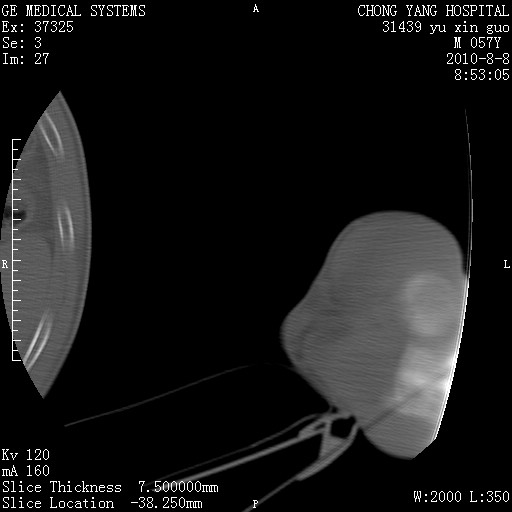

标题: CT28267:M57Y 上臂包块8年余。 [打印本页]

标题: CT28267:M57Y 上臂包块8年余。

包膜光滑、完整的脂肪密度肿块,支持脂肪瘤。

脂肪瘤。有ct值?